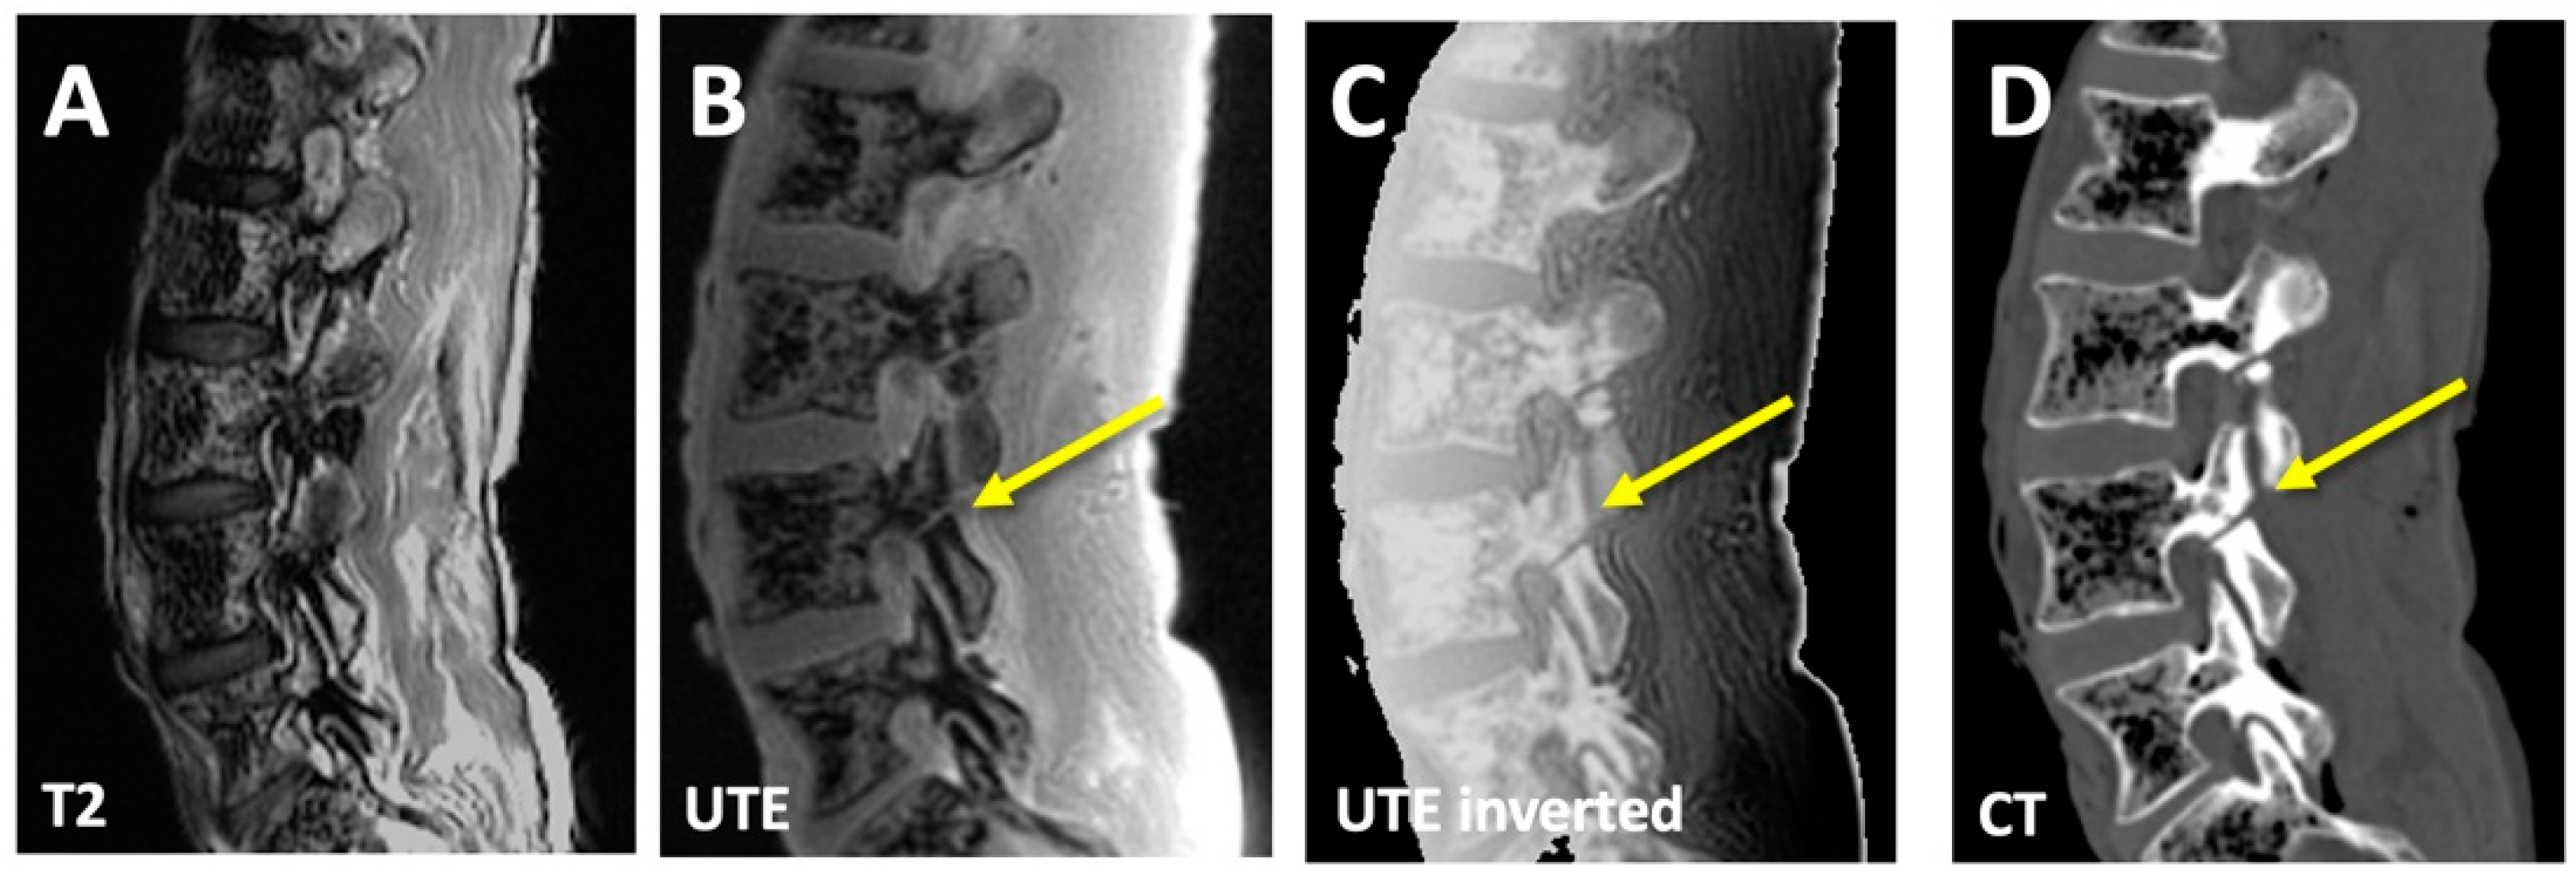

3.1. CT-like Images